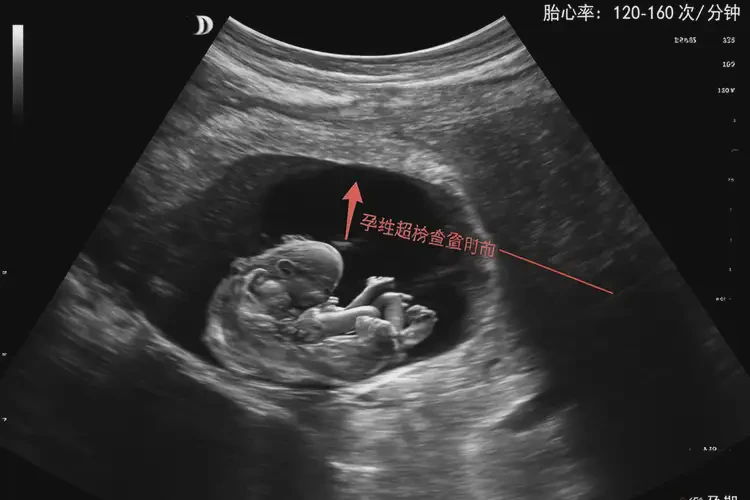

胎心率是指胎兒心臟每分鐘跳動的次數(shù),正常范圍在120-160次/分鐘之間。在懷孕早期,尤其是10周左右,胎心率可能會稍高一些,達(dá)到170-180次/分鐘也是常見的。胎心175次/分鐘在懷孕10周時并不意味著胎兒有危險,通??梢岳^續(xù)觀察。

• 懷孕10周時,胎心率的正常范圍通常在120-160次/分鐘之間。

• 由于胎兒的心臟在早期發(fā)育階段尚未完全成熟,胎心率可能會稍高一些。

懷孕10周胎心175還能保住嗎(圖1)